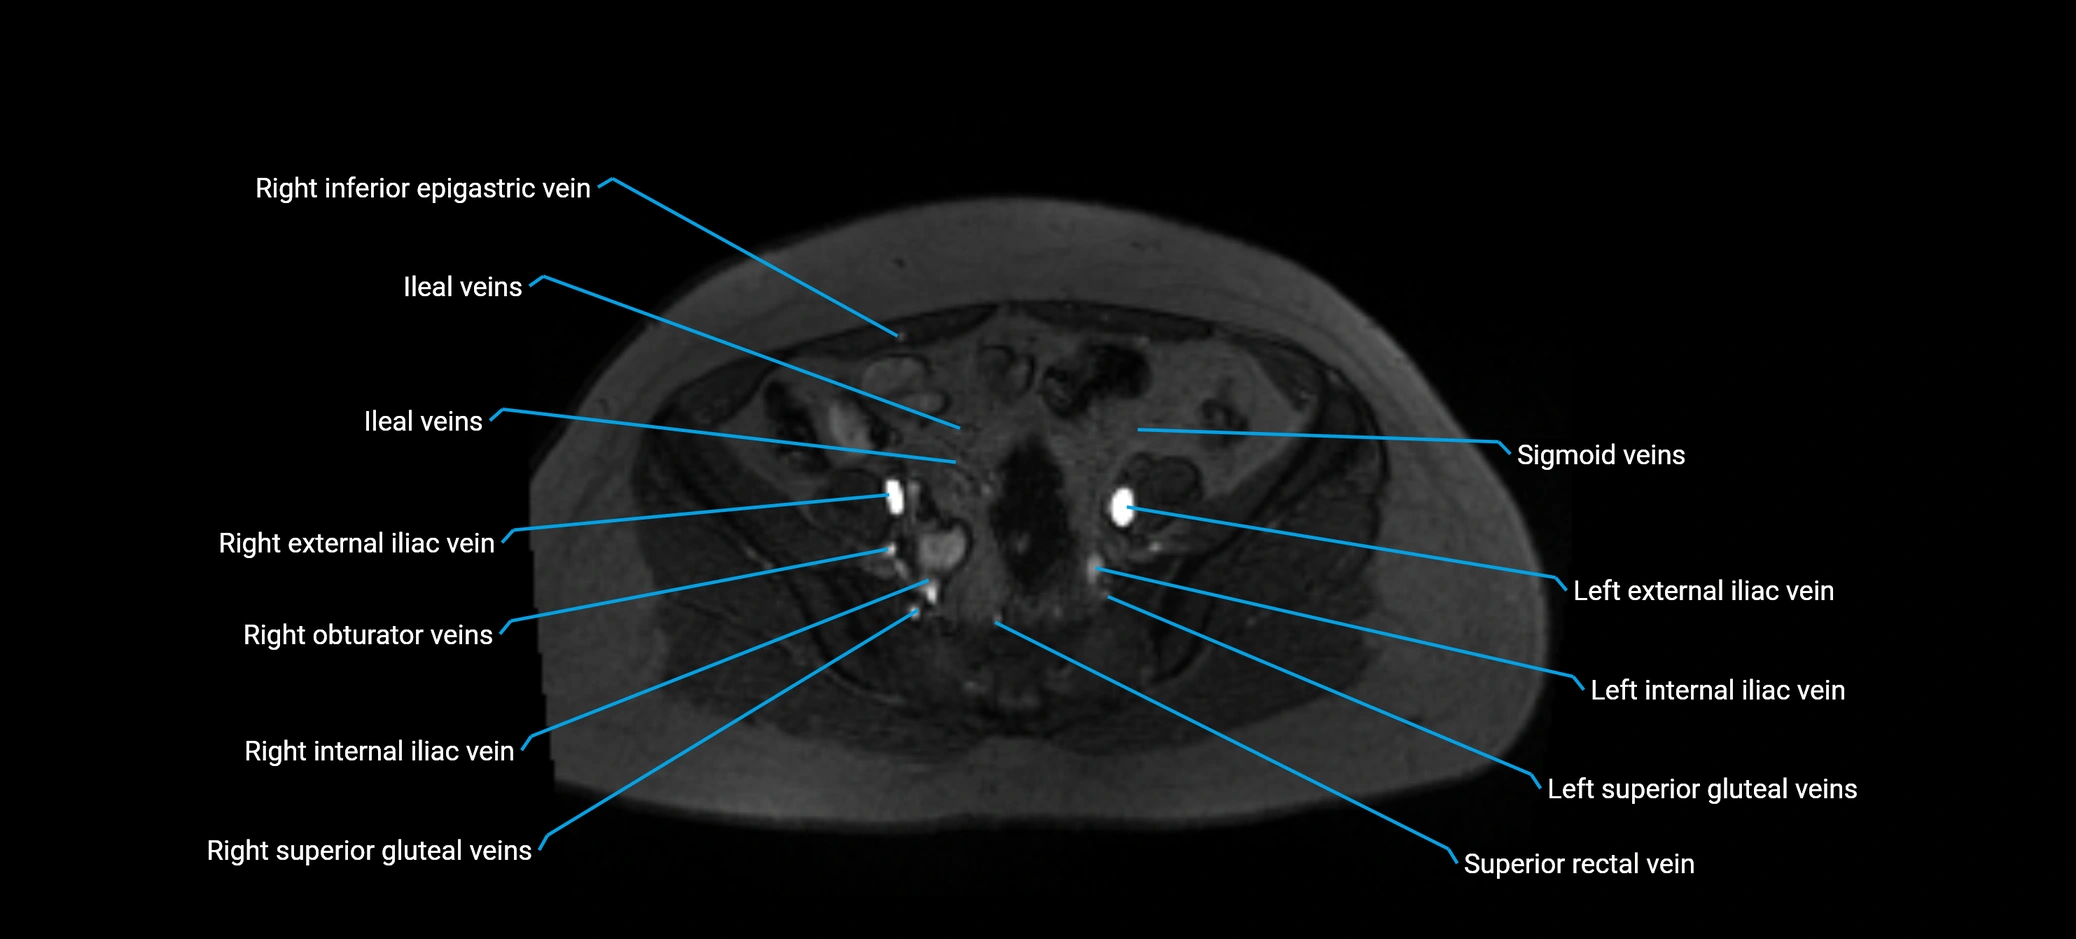

MRI image

image